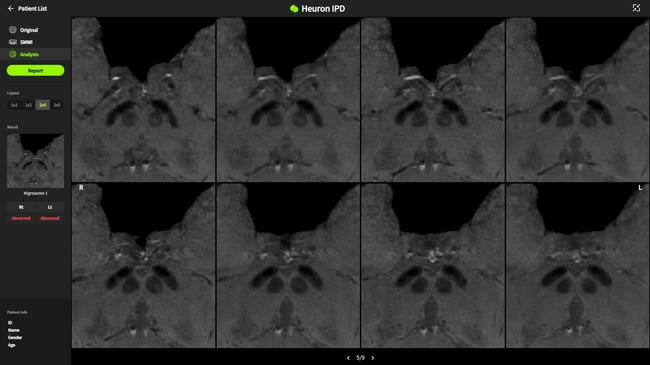

휴런, 파킨슨병 솔루션 ‘휴런IPD’ 이미지

뇌신경 질환 전문 의료 인공지능(AI) 기업 ㈜휴런은 최근 파킨슨병 솔루션인 휴런IPD(Heuron IPD)로 싱가포르 인허가를 획득했다고 밝혔다.

휴런IPD는 MRI를 기반으로 파킨슨병을 진단 보조하는 AI 솔루션으로, 기존 핵의학 검사 대신 3.0T MRI만을 사용해 나이그로좀 영역의 이상을 판별하는 방식이다. 이 솔루션은 경제성과 접근성이 뛰어나며 방사선 노출이 적어, 파킨슨병 진단에 중요한 바이오마커로 활용되는 나이그로좀 영역의 변화를 효율적으로 분석할 수 있다.

휴런IPD는 싱가포르 보건과학청(HSA)으로부터 Class B 등급을 획득하며, 올해부터 싱가포르의 병원과 검진센터 등에서 본격적으로 상용화될 예정이다. 또한 휴런은 싱가포르 내 저명한 파킨슨병 연구자들과 협력해 임상 근거 확보를 위한 연구를 진행 중이다. 지난해에는 싱가포르 종합병원의 링링 찬 교수 연구팀과 함께 휴런IPD를 활용한 연구를 성공적으로 마친 바 있다.

신동훈 휴런 대표는 “싱가포르는 휴런의 파킨슨병 솔루션 연구개발 및 사업 전반에서 중요한 시장”이라며 “이번 인허가 획득을 계기로 휴런IPD가 싱가포르 내에서 더욱 널리 사용될 수 있기를 바라며, 싱가포르 법인을 중심으로 아시아 시장 진출을 가속화할 것”이라고 밝혔다.